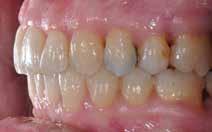

Den kliniske undersøgelse viser harmoniske ekstraorale sagittale forhold med skeletalt dybt bid (Fig. 1A, D). Hendes smil er alderssvarende med en eksponering på 8/10 af overkæbeincisiverne, mens smilets bredde er smalt med synlige mørke laterale rum (Fig. 1D). Underkæbeincisiverne er synlige under tale. Der ses neutrale okklusale forhold ved hjørnetænderne og neutrale pladsforhold i overkæben, men udtalt trangstilling i underkæben især lokaliseret i regio 1-1 (Fig. 1C).

Sliddet klassificeres som grad 2 (moderat tandslid) på de centrale incisiver i overkæbe og underkæbe. Det kan anses som patologisk, da det er atypisk for patientens alder, giver anledning til smerte/ubehag, og giver patienten et æstetisk problem. Der ses infraktioner af overkæbeincisiverne. Der ses endvidere en udtalt Spee-kurve i underkæben og ingen interincisal afstøtning på 2-2 med let ganepåbidning.

Røntgenanalyse viser fravær af -6 samt et velholdt tandsæt uden tegn på sygdom. Profilrøntgenbilledet viser et skeletalt

dybt bid, men normal inklination af fortænder i over- og underkæbe (Fig. 1B).